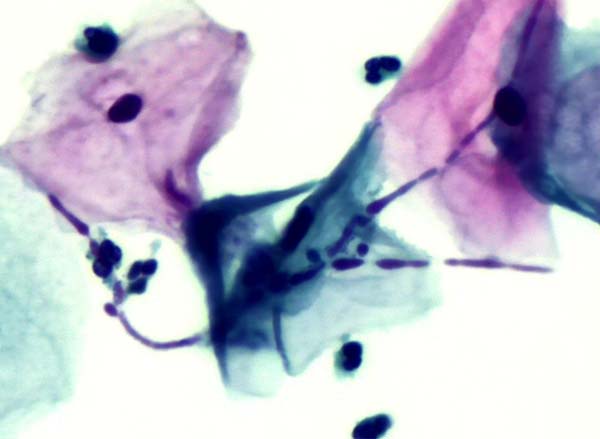

霉菌感染

霉菌在宫颈样本中通常是由于念珠菌感染导致,主要的表现是剧烈的瘙痒感、红肿和灼烧感。